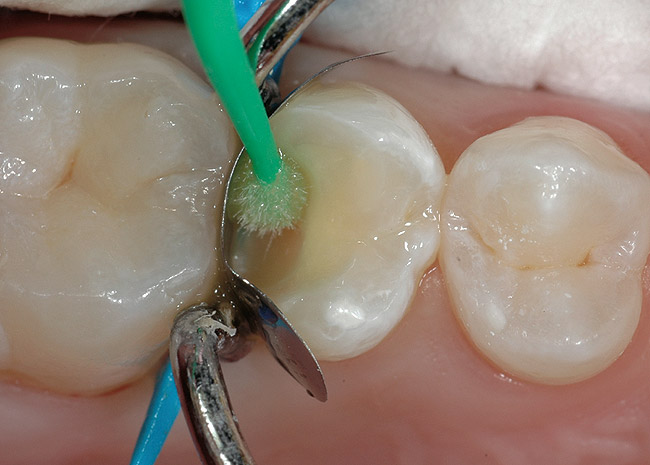

Figure 17  Phosphoric acid (30% to 40%) is ringed on the enamel first for 15 seconds and then run into the tooth for approximately another 10 seconds. It is then washed out, the tooth is briefly dried, and the restoration is finished using primers and adhesives.

Figure 17

Figure 18  Phosphoric acid (30% to 40%) is ringed on the enamel first for 15 seconds and then run into the tooth for approximately another 10 seconds. It is then washed out, the tooth is briefly dried, and the restoration is finished using primers and adhesives.

Figure 18

Figure 19  Phosphoric acid (30% to 40%) is ringed on the enamel first for 15 seconds and then run into the tooth for approximately another 10 seconds. It is then washed out, the tooth is briefly dried, and the restoration is finished using primers and adhesives.

Figure 19

Figure 20  Phosphoric acid (30% to 40%) is ringed on the enamel first for 15 seconds and then run into the tooth for approximately another 10 seconds. It is then washed out, the tooth is briefly dried, and the restoration is finished using primers and adhesives.

Figure 20

Figure 21  Phosphoric acid (30% to 40%) is ringed on the enamel first for 15 seconds and then run into the tooth for approximately another 10 seconds. It is then washed out, the tooth is briefly dried, and the restoration is finished using primers and adhesives.

Figure 21